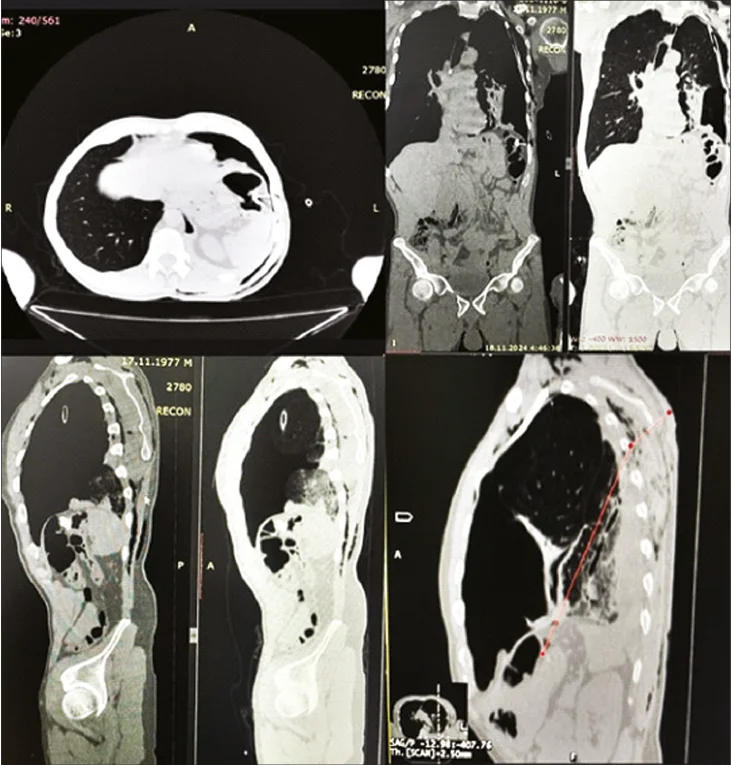

З метою інструментального обстеження пацієнту була проведена комп’ютерна томографія (КТ). Результати обстеження показали наступні зміни: проникаюче вогнепальне поранення з внутрішнім і зовнішнім ушкодженням нижньої частки лівої легені, перфорація діафрагми зліва, перфорація поперечно-ободової кишки із залишеним металевим фрагментом; пневмоперитонеум, дренований гемопневмоторакс, вогнепальний перелом задньої третини V лівого ребра (рис. 1). Лапароскопічна операція була запланована, оскільки пацієнт був гемодинамічно стабільним і без ознак системної запальної відповіді та вільної рідини в черевній порожнині .

Рис. 1. Зображення КТ: наскрізне вогнепальне поранення з внутрішнім і зовнішнім ушкодженням нижньої частки лівої легені, перфорація діафрагми зліва, перфорація поперечної ободової кишки із присутнім металевим фрагментом